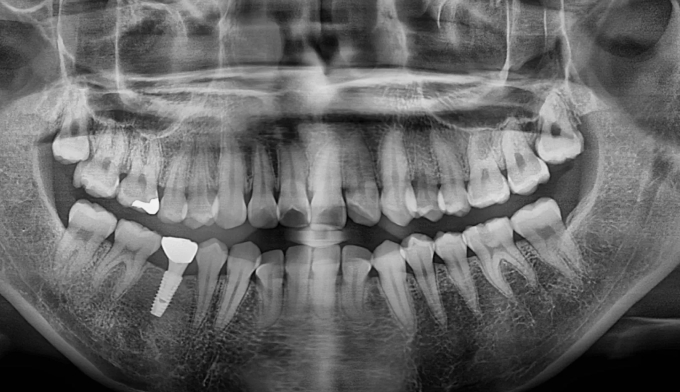

돌출입과 불규칙한 앞니를 가지고 있습니다. 그리고 아래쪽에 ‘임플란트’가 있습니다.

임플란트는 뼈와 강력히 결합되어 있기 때문에 교정치료로 절대 움직일 수 없습니다. 따라서 해당 부위는 절대 교정치료로 움직일 수 없다는 제한점이 있는 상태에서 교정치료를 진행하게 되었습니다.

돌출입을 해소하고 앞니를 가지런하게 만들기 위한 공간을 만드는 과정중에는 저 임플란트를 꼭 제거해야 했으나, 최대한 발치 없이 교정을 진행하였습니다.

후방이동이 불가하므로 악궁확장을 통하여 공간확보를 시도하였고, 동시에 돌출감도 해소되었습니다.

최종적으로 임플란트의 존재때문에 중심선을 맞추지는 못했으나 환자분은 너무 만족해하셨습니다.

임플란트가 있다고 무조건 교정을 못하는것은 아닙니다.

총 치료기간은 14개월 소요되었습니다.